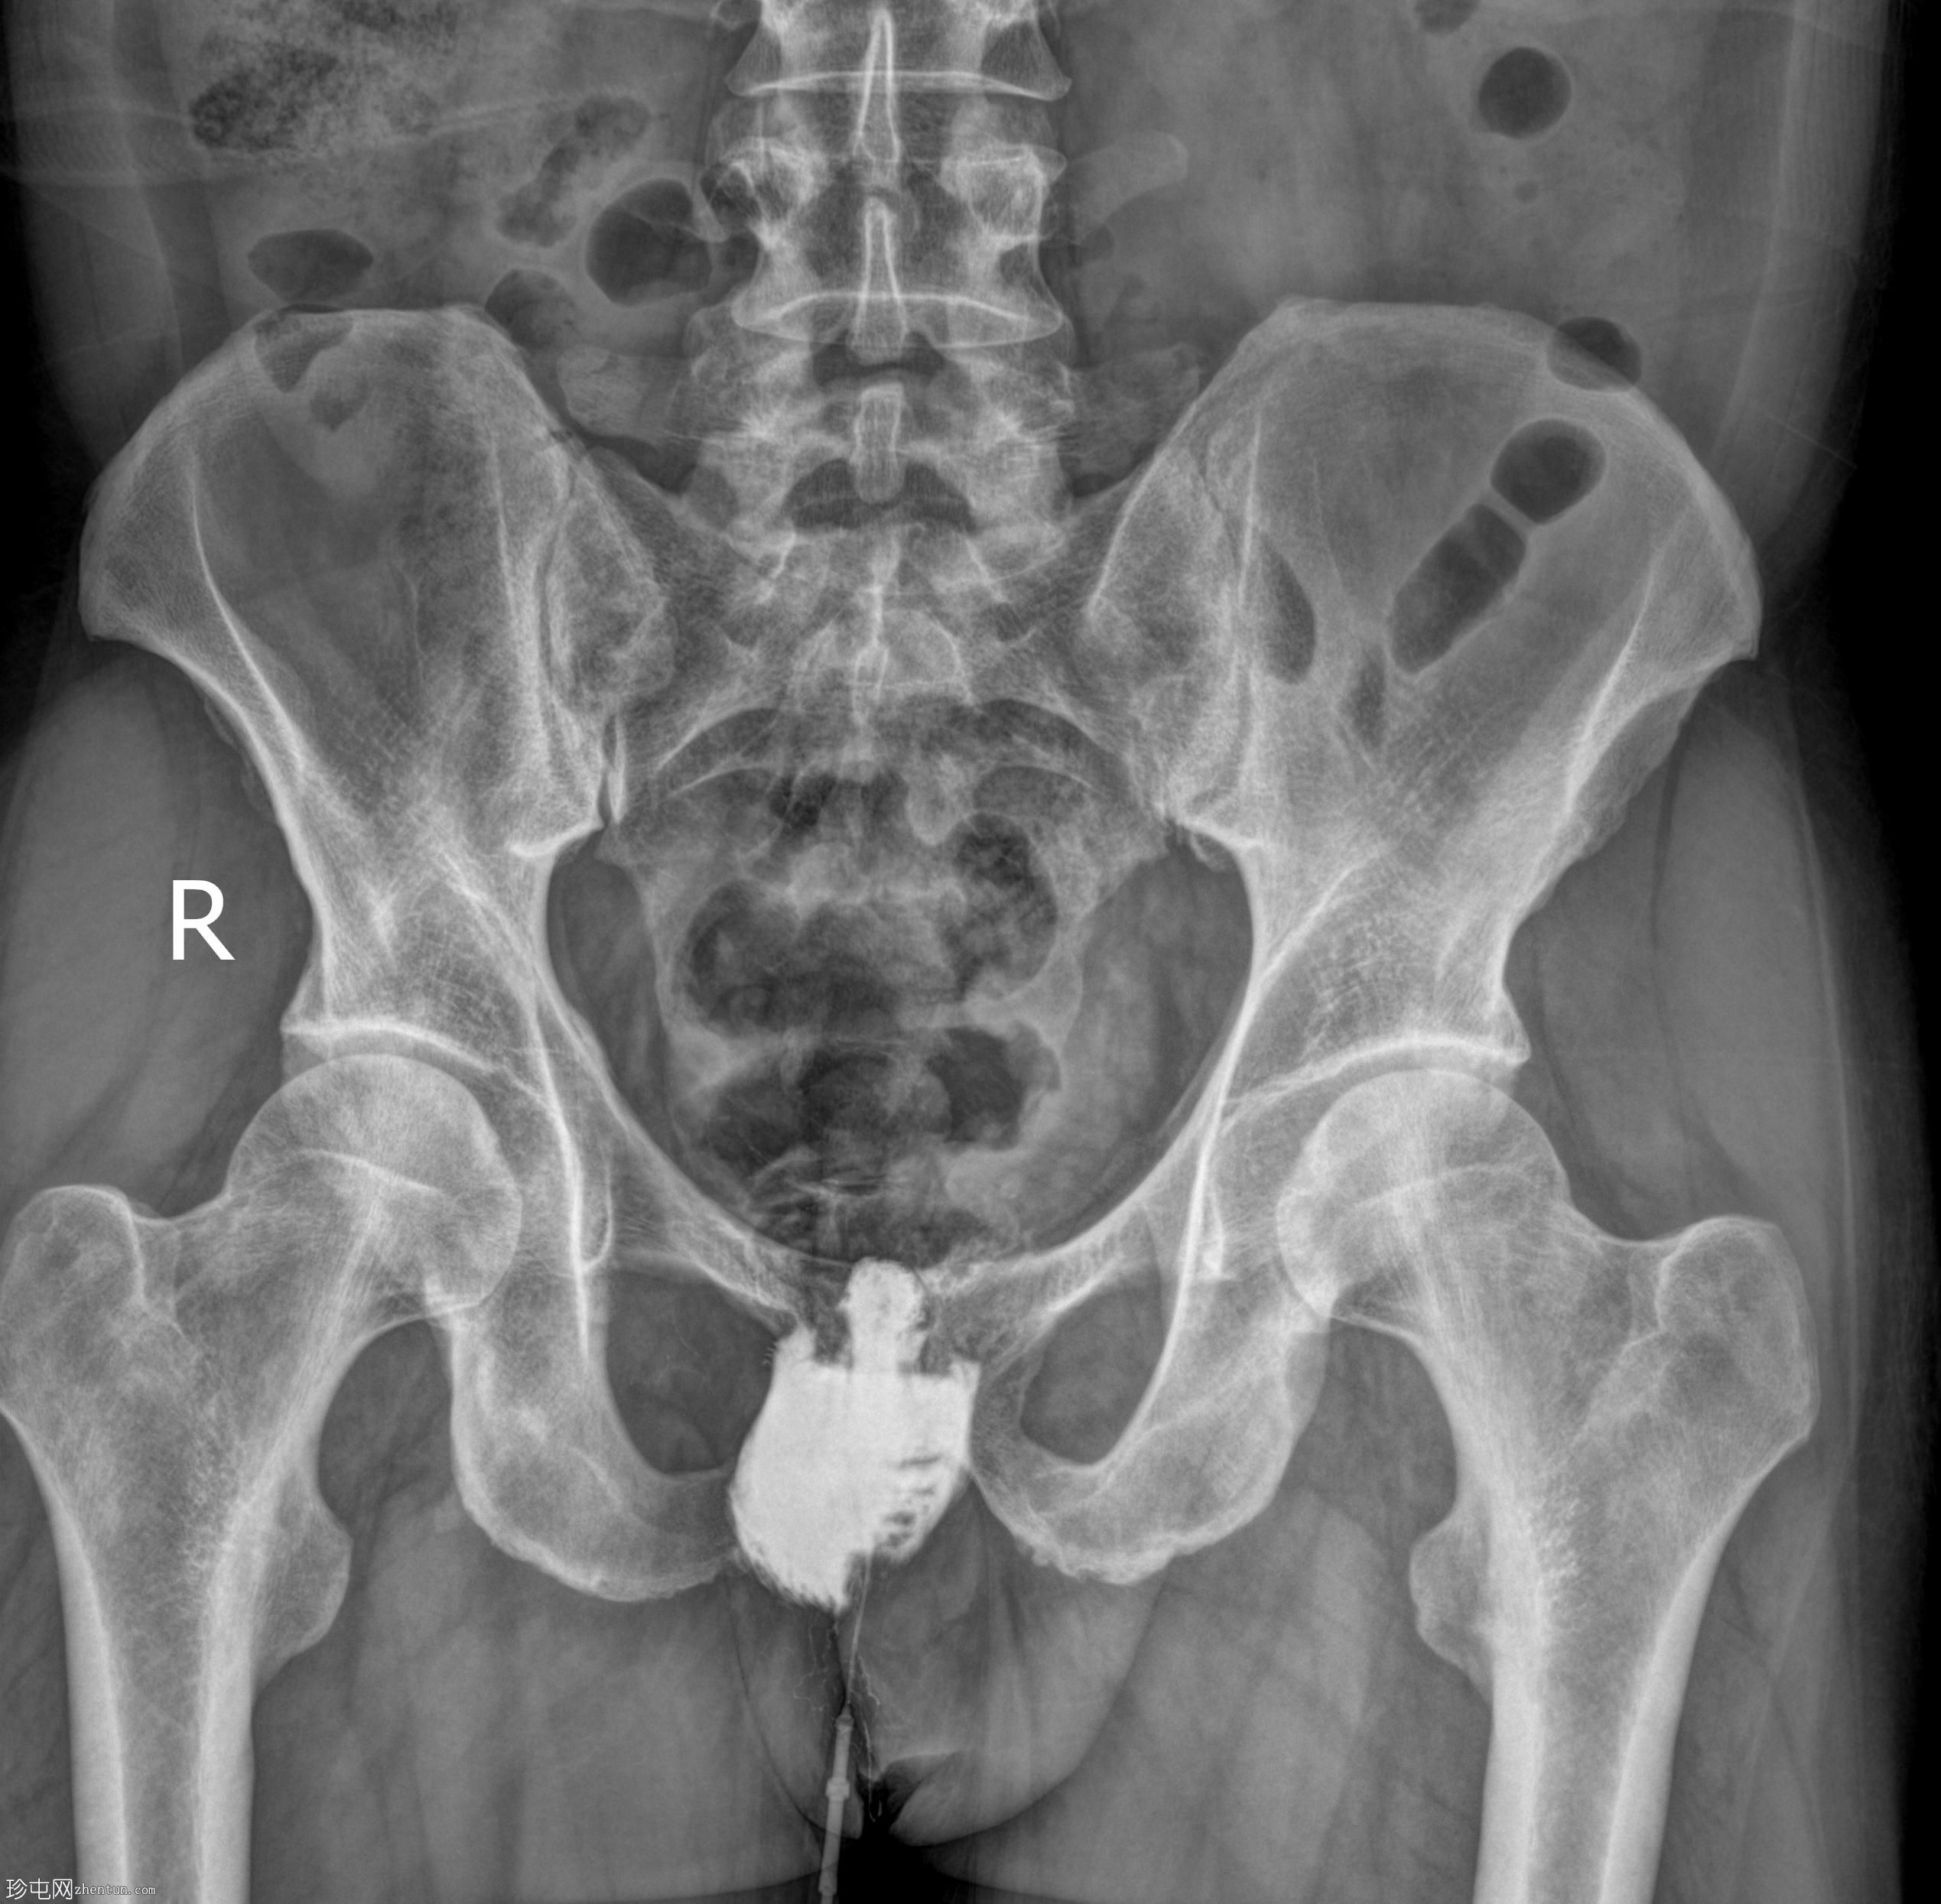

正位

经脓性分泌物开口注入造影剂,显示右侧肛周脓肿显影。

未见造影剂明显外渗至肛管或直肠。

透视瘘管造影图像显示右侧肛周脓肿较大,与肛管或直肠无交通。